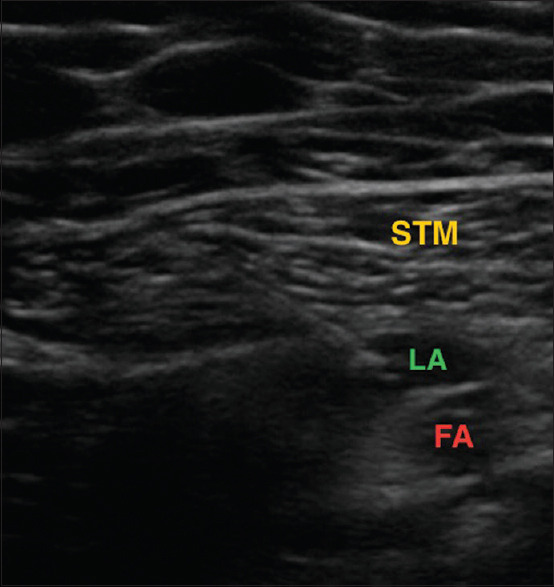

Material and methods: Sixty patients aged 18-80 years and ASA grade I-III undergoing unilateral TKA were randomised to two groups postoperatively to receive DSB or SSB. Patients in group DSB received distal femoral triangle block (15 ml) + proximal adductor canal block (20 ml), while group SSB received only proximal adductor canal block (20 ml). Primarily, the changes in pain intensity and pain control in terms of static and dynamic visual analogue score (VAS) with the duration of analgesia and cumulative dose requirement of rescue analgesic in the first 24 hours postoperatively were studied. Secondary outcomes were the postoperative degree of motor blockade, the ability of early ambulation, patient satisfaction and complications. Statistical analysis was done using the student t-test and Chi-square test using MedCalc version 12.4.3.0.